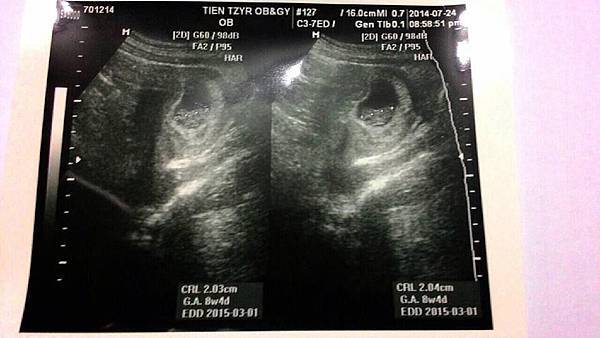

今天已經8W4D了 可以拿到媽媽手冊 也進行第一次正是產檢

所以看醫生前 要憋尿 照腹部超音波檢查心跳跟小B仔 還要驗血+驗尿

同時我們自費2000元檢查 "

SMA脊髓性肌肉萎縮症基因確認診斷"